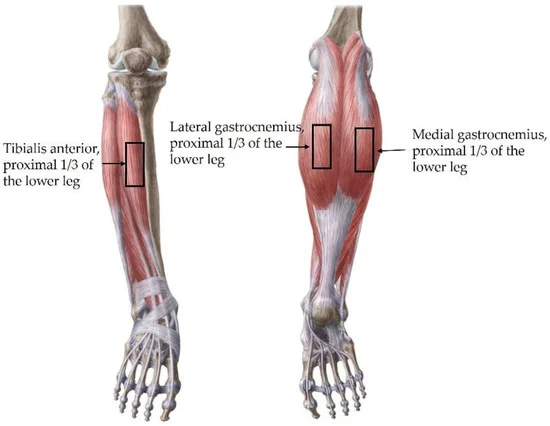

前脛骨筋:参加者を仰臥位にして、膝蓋骨の下縁と第一中足骨基部の間の距離の1/3の地点での硬さを測定した。

腓腹筋:うつ伏せにした状態で測定した。腓腹筋内側頭は膝蓋骨の内側から踵までの距離の1/3の位置で、腓腹筋外側頭は膝蓋骨の外側から踵までの距離の1/3の位置で測定した。